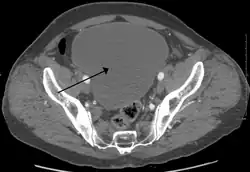

![]() | |

Urinary retention with greatly enlarged bladder as seen by CT scan. | |